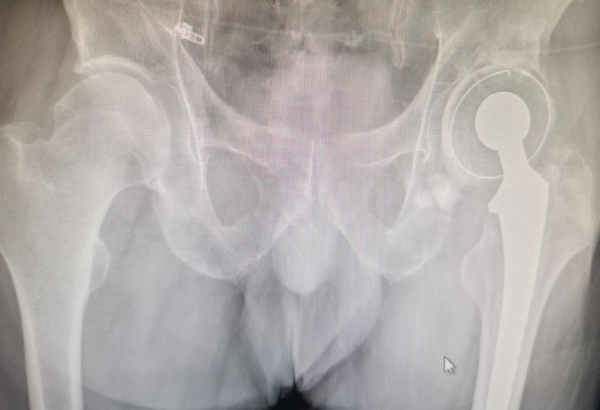

患者术前X线

近日,家住齐齐哈尔市的张大爷因左侧髋关节疼痛难忍,慕名来到齐医附属二院骨外科四病区(运动医学科)就诊,李宝权主任通过询问张大爷病史得知,该患者13年前因外伤导致左侧股骨颈骨折,行全髋关节置换手术治疗,近期感到左髋关节疼痛明显伴有习惯性脱位,导致不能行走,严重影响日常生活。李宝权主任带领团队认真研究患者病情,对患者进行了仔细查体,结合影像检查,经过充分考虑并与患者沟通后,决定为其行全髋关节假体翻修术。在李宝权主任团队及麻醉师、手术室的共同配合下,经过三个多小时紧张的手术,张大爷安全平稳的返回病房。术后患者恢复良好,左侧髋关节疼痛症状完全缓解,张大爷激动的表示自己的腿不疼了,衷心感谢齐医附属二院骨外科四病区李宝权主任团队的付出。

全髋关节假体翻修术原因包括假体松动、假体周围骨折、假体周围感染等,所有翻修手术因大多都存在不同程度骨缺损,如何重建骨缺损通常是比较困难的挑战。

髋关节翻修术是关节外科医师所面临的挑战,术中稍有处理不当就会导致假体早期松动致翻修术失败。人工髋关节置换术后翻修对于关节外科医师仍然是极具挑战的难题,其不仅在于手术的难度,更在于对初次手术失败原因的判断、骨缺损的评估、手术方式和假体的选择等问题。